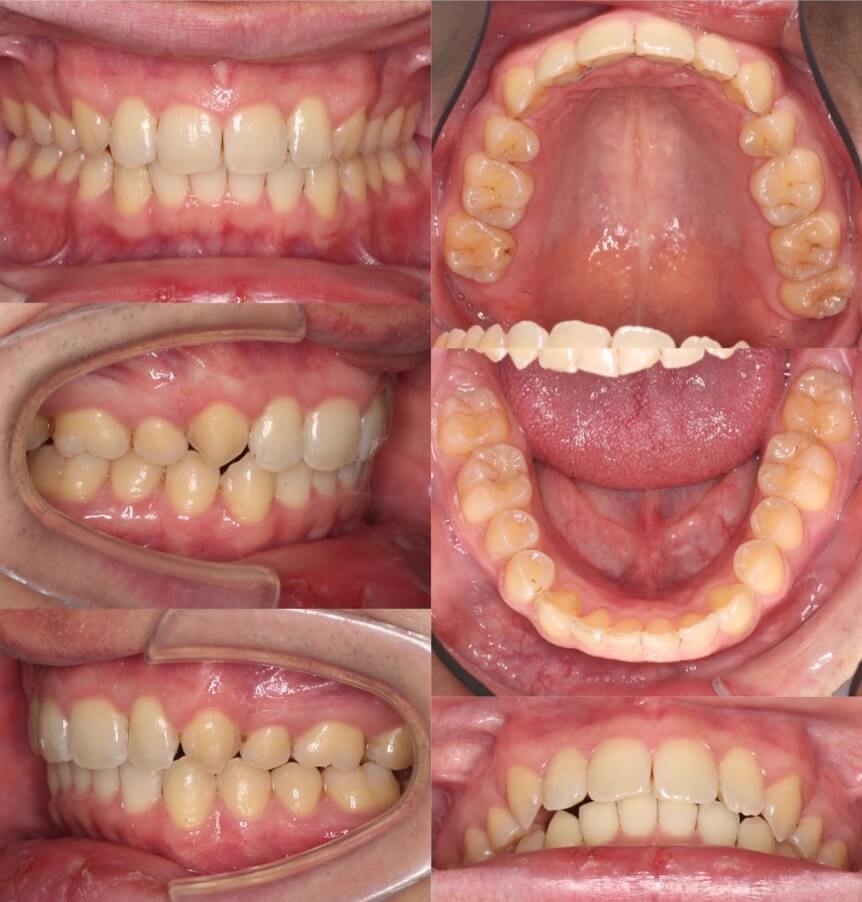

20代女性・ハーフリンガル・4本抜歯

過蓋咬合の抜歯症例は、マウスピース型矯正装置や上下の裏側装置での矯正治療は非常に難易度が高くなります。そこで上だけ裏側装置を使用したハーフリンガルにする事で、前歯のかみ合わせのコントロールを行いました。治療期間はかかりましたが、無事矯正治療を終える事ができました。

<症例概要>

主訴:前歯のでこぼこ

年齢・性別:20代女性

住まい:千葉県船橋市

症状:過蓋咬合・叢生・上顎前突

治療方針:抜歯空隙の閉鎖(最大固定)

治療装置:ハーフリンガル矯正装置(上のみ裏側装置)

固定装置:歯科矯正用アンカースクリュー(口蓋側壁x2)

抜歯:上下左右4番(計4本)

治療期間:3年1か月

リテーナー:上下フィックスタイプ+プレートタイプ+クリアタイプ

治療費用:1,495,000(税込)

代表的副作用:痛み・治療後の後戻り・歯根吸収・歯髄壊死・歯肉退縮

▶︎その他の副作用